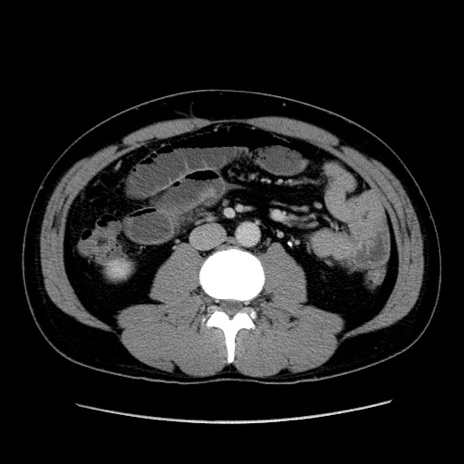

症例4(横断像)

【症例】30歳代男性

【主訴】腹痛、嘔吐

【現病歴】昨晩から突然の腹痛あり、その後嘔吐、軟便も出現。腹痛が改善しないため救急搬送となる。2日前にしめ鯖の食事歴あり。

【身体所見】意識清明、苦悶様、BP 135/90mmHg、BT 35.7℃、腹部:平坦、やや硬、心窩部〜臍部に自発痛、圧痛あり、筋性防御+、反跳痛-

【データ】WBC 8100、CRP 0.57